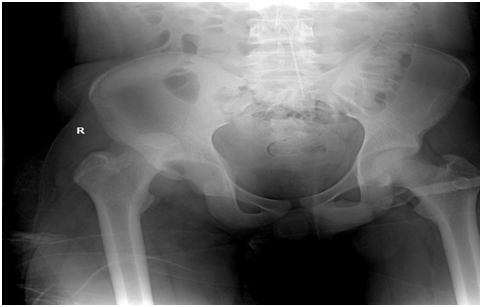

1. After 2 months patient is seen in clinic with full range of movement and start partial weight bearing,

2. After 3 months patient is seen in clinic with full range of movement hip and no sign of avascular necrosis head femur and full weight bearing is started,

3. After 4 months patient is doing fine, walked full weight bearing, and still am doing follow up to the patient (Figures 1-4).

Figure 4 Neglected  recurrent fracture dislocation hip After 3 Monthes.